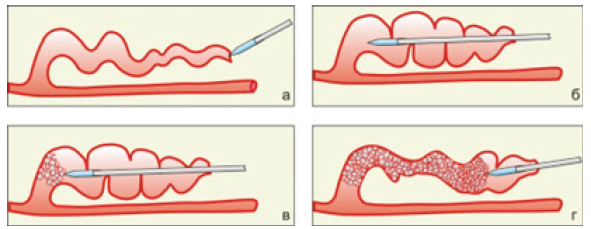

A puncture of the skin with an 18 G needle was performed over a pronounced convoluted vein. Through this puncture, controlled by ultrasound scanning, a puncture of the distal section of the altered vein was performed with a 60-degree sharpened tip of an optical fiber. Next, the light guide moved in the direction from the main vein, along the modified vein, for its entire length. The vein was impaled on the light guide and positioned (skewer-ablation) (Figure 1).

Between the anterior wall of the vein and the skin, tumescent anesthesia (not tight or tense) is performed with a cooled solution - 50 ml of 4% soda solution (sodium bicarbonate) and 20 ml of 2% lidocaine are added to 1liter of saline solution (0.9% sodium chloride solution). The solution is not injected under the vein. In this case, the saline solution does not compress the vein around the light guide. After that, laser radiation with a wavelength of 1.47 microns and a power of 6 - 8 watts is fed into the fiber and the fiber begins to move inside the vein lumen to the skin puncture site, bringing it out.

The paper provides a physical substantiation of a new technology for the treatment of varicose veins - superficially located tributaries of the main veins by endovascular laser ablation, which is devoid of the disadvantages of miniflebectomy and sclerobliteration, namely, the painfulness of the procedure, damage to perivascular vessels, nerves, subcutaneous fat, postoperative hematomas, infection of postoperative wounds, scars in places of micro-incisions, frequent relapses of the disease, the formation of “coagules” inside the lumen of the vein, hyperpigmentation and necrosis of the skin [10-20]. The new ELTA technology does not use conventional optical fibers with a “radial” nozzle and end-type fibers. For the treatment of varicose veins - superficially located tributaries of the main veins, since the use of “radial” optical fibers leads to overheating and burning of perivascular tissues, and the use of end-type fibers is difficult due to the high degree of tortuosity of surface veins.

In this regard, the “Skewer” technology was proposed, which is based on the use of a cone-sharpened tip of the end fiber, with which a convoluted surface vein is strung on the fiber, like on a skewer. The aim of the study is to show that heat flows arising from the boiling of blood on laser heating elements made in the form of a cone-sharpened tip of the end fiber cannot lead to overheating and burning of perivascular tissues, as is the case of a “radial” nozzle fiber.

The lumen of the ablated vein is compressed due to the evaporation of the liquid component of the blood, denaturation of blood proteins and endothelium; the lumen of the vein is filled with protein foam and detritus. Over time, the vein becomes scarred. The proposed method of laser ablation of strongly convoluted veins does not require additional tools (conductors, catheters or introducers, etc.), since the passage of the light guide inside the vein and in the perivascular tissues is carried out via the compacted working part of the light guide, pointed at an angle of 60 degrees; it ensures a low injury rate and a good cosmetic effect, reduces the duration of treatment and recovery of patients, as well as the occurrence of hemorrhages and hematomas.